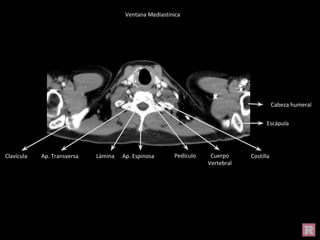

Ventana Mediastínica

Tráquea

Vena Yugular

Interna

Carótida

Arteria

axilar Cabeza

humeral

Escápula

Costilla

Clavícula

Ap. Transversa Lámina Ap. Espinosa

Pedículo

Cuerpo

Vertebral

Cabeza humeral

Clavícula Ap. Transversa Lámina Ap. Espinosa Cuerpo